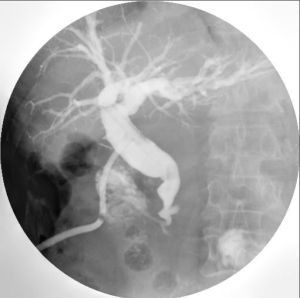

經T形管膽囊造影膽囊手術後留有“t”形引流管,一般術後1-2周內準備撥管前由引流管注入造影劑觀察膽管情況。造影前套用生理鹽水沖洗膽管,並避免進入氣泡。造影劑可用12.5%碘化鈉水溶液,或含碘有機化合物水溶劑,注藥後立即照片。本法顯示膽管清楚,並可顯示肝內膽管的分支。用以觀察膽管內有無殘留結石,了解膽管的擴張、狹窄及通暢情況等是指觀察膽管內殘留結石或其他疾病,以及了解膽管及十二指腸的通暢情況。

膽囊正常膽管:靜脈法造影一般在注藥後30-40min,總膽管及總肝管顯示較為清楚,以後漸不清晰。口服法造影總膽管顯影僅在脂餐後照片可能見到。各種直接顯示膽管的造影效果較好,除見總膽管、總肝管外,並可見左、右肝管及其肝內的一些分支。正常膽管充盈時輪廓光滑、粗細勻稱、密度均勻。總膽管的寬徑(直徑)一般為0.5-0.7cm(靜脈法),直接膽管造影較靜脈法所見者稍寬,但不應超過1.2cm。膽囊管寬約0.2-0.3cm,可見螺鏇皺襞。